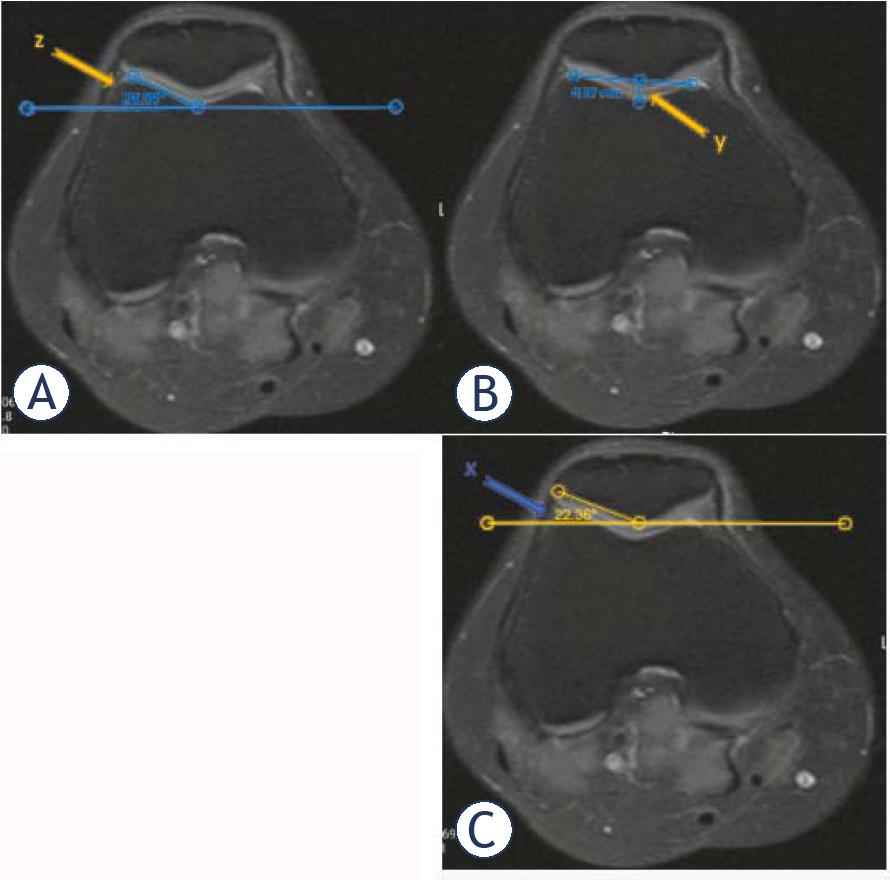

(A, B, C) Axial PD fat sat MR images illustrating lateral trochlear inclination, trochlear depth, and lateral patellofemoral angle. (Lateral trochlear inclination, z: the angle formed between the lateral trochlear facet and a parallel line to the line connecting the posterior-most cortical surfaces of the femoral condyles; Trochlear depth, y: the distance between the deepest point of trochlear sulcus and the line connecting the anterior points of the medial and lateral condyles; Lateral patellar tilt angle, x: the angle between the line parallel to the patellar lateral facet and the line connecting the most posterior parts of femoral condyles)